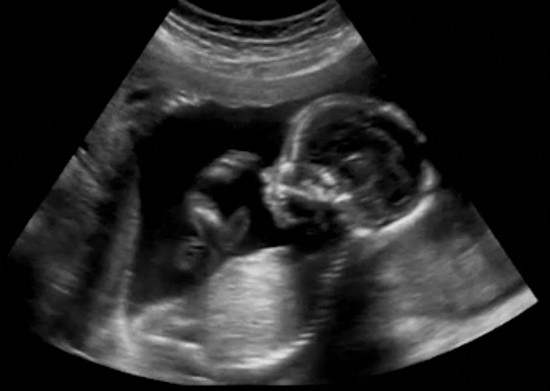

There is a good chance the 2017 Legislature will pass an NH fetal homicide law.  Such a law allows prosecutors to file murder charges if a pregnant woman is the victim of a crime and her fetus does not survive.

The Legislature came very close to passing a fetal homicide law in 2015 and 2016, but the House and Senate could not agree on whether the law should apply to “viable fetuses” – fetuses capable of surviving outside the womb – or fetuses eight weeks and older.  Part of the challenge was the threat of a veto from Democratic Gov. Maggie Hassan, who was unlikely to support a broad fetal homicide bill.

Rep. Jeanine Notter has accordingly sponsored a 2017 bill to include fetuses eight weeks and older as potential victims, HB 156.  A similar bill in the Senate, SB 66, would apply to "viable fetuses." SB 66 bill recently received an ‘ought to pass’ recommendation from the Senate Judiciary Committee.

Although fetal homicide laws are written to exclude legal abortions, opponents argue that the laws are a backdoor way to give fetuses the same rights as people.  Broadly written fetal homicide laws may even be used to prosecute mothers for behavior that leads to miscarriage.

Supporters of fetal homicide laws argue that unborn children can absolutely be the victims of murder.  They point to cases such as the brutal attack on Michelle Wilkins in Colorado, whose baby was cut from her stomach and left for dead in a bathtub.